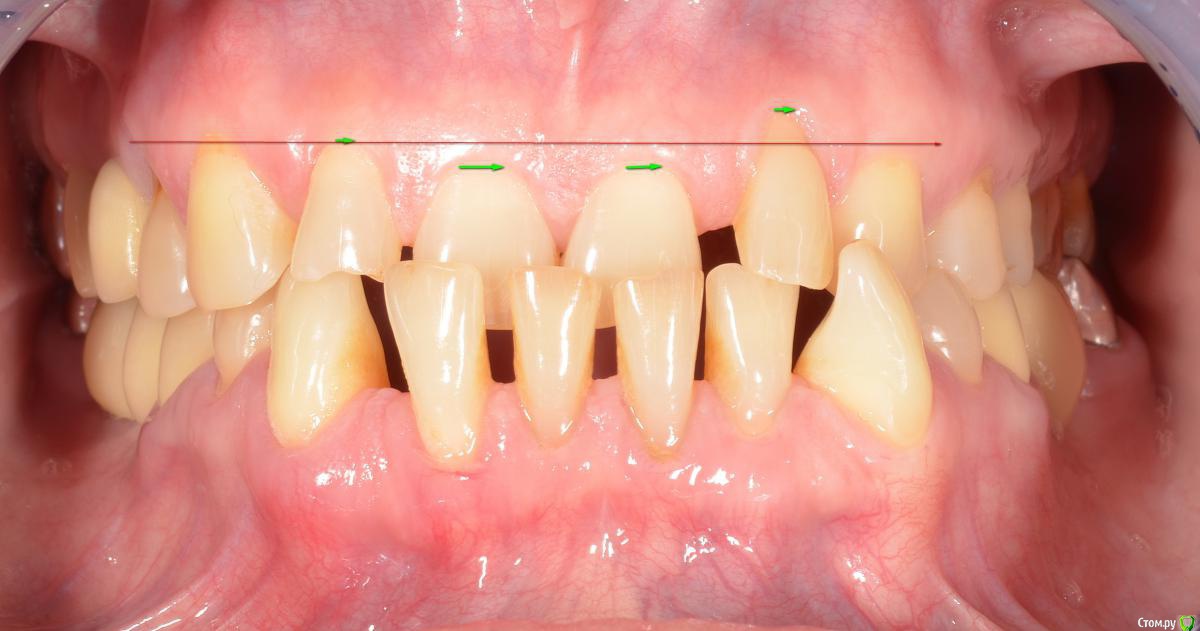

pit Опубликовано 5 октября, 2017 Поделиться Опубликовано 5 октября, 2017 Если без ортодонта и по простому, я бы в первую очередь загипсовал бы в артикулятор (или хотя бы в хлопушку), поднял бы высоту прикуса на 5-6 мм и прикинул бы что к чему ( какие зубы спилить, какие удлинить). Оценил бы ОПТГ, наверняка какие-нибудь зубы нужно будет удалить. На основании этого уже бы заказывал моделировку зубов в ЗТЛ, а после анализа воска снимал бы старые коронки. Не считая что нужно сделать тотал, проблема в 3-х зубах верхней челюсти и 3-х зубах нижней. Какие-то из них удалить, а оставшимся изменить наклоны вкладками. 6 Ссылка на комментарий

Kazankov.Egor Опубликовано 6 октября, 2017 Поделиться Опубликовано 6 октября, 2017 Если без ортодонта и по простому, я бы в первую очередь загипсовал бы в артикулятор (или хотя бы в хлопушку), поднял бы высоту прикуса на 5-6 мм и прикинул бы что к чему ( какие зубы спилить, какие удлинить). Оценил бы ОПТГ, наверняка какие-нибудь зубы нужно будет удалить. На основании этого уже бы заказывал моделировку зубов в ЗТЛ, а после анализа воска снимал бы старые коронки. Не считая что нужно сделать тотал, проблема в 3-х зубах верхней челюсти и 3-х зубах нижней. Какие-то из них удалить, а оставшимся изменить наклоны вкладками.Если Вы говорите о изменении vdo на 5-6 мм, то скорее всего речь идёт от измении во фронтальном отделе, так как в стандартном артикуляторы 1мм в жевательной отделе даст порядка 3мм во фронте. Удобно пользоваться одноразовыми шпателями для разобщения во фронтальном отделе, это даст примерное понятие о нужной высоте в жевательном отделе. Начинать такой кейс стоит с фиксации моделей в артикулятор по дуге, hip и др. Далее убедиться в стабильности положения нижней челюсти, для этого отожмите пресс-капу на любую из челюстей (я обычно выбираю челюсть с большим количеством отсутствующих зубов) и изготовьте передний депрограмматор, отдайте на неделю ночного сна, достройте полный ортотик прямо во рту и пришлифовывайте его до окончания миграции контактов. Зафиксируйте соотношение. Далее воск/пришлифовывайте и Вам уже виднее, я не ортопед))) 2 Ссылка на комментарий

iya Опубликовано 28 ноября, 2017 Поделиться Опубликовано 28 ноября, 2017 (изменено) Хирургически поднять зениты у передних зубов справа, чтобы выровнять линию улыбки. Изменено 28 ноября, 2017 пользователем iya Ссылка на комментарий

gum Опубликовано 4 декабря, 2017 Поделиться Опубликовано 4 декабря, 2017 Поддерживаю решение с поднятием зенитов, но только, как сказал Dr.Stomatolog, после полноценной диагностики и с поднятием окклюзии.Вообще столько времени прошло, что-то сделали или нет? Ссылка на комментарий